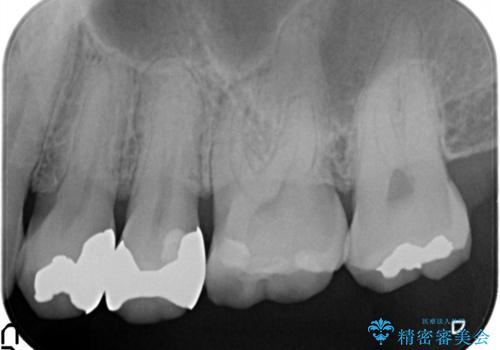

- 銀歯を白くしたい。水が少し染みるとの事で来院。

歯と歯茎の境目にプラスチック樹脂の治療の後があり、そこが染みる原因となっていました。

拡大鏡下で銀の詰め物、古いプラスチックの樹脂を外し、虫歯が残ってないかを確認して

ジルコニアクラウンで治療を行いました。